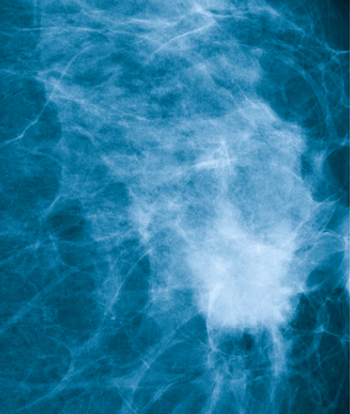

Oral agents and “watchful waiting” might make it possible to delay or avoid overtreatment with surgery and radiotherapy for many women diagnosed with ductal carcinoma in situ.

Not all DCIS is dangerous, and the prognostic genomic Oncotype DX DCIS Score allows for routine risk stratification of patients to avoid unnecessary treatment.